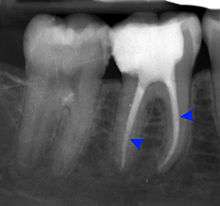

Apical periodontitis

Apical periodontitis is acute or chronic inflammation around the apex of a tooth caused by an immune response to bacteria within an infected pulp.[19] It does not occur because of pulp necrosis, meaning that a tooth that tests as if it's alive (vital) may cause apical periodontitis, and a pulp which has become non-vital due to a sterile, non-infectious processes (such as trauma) may not cause any apical periodontitis.[9]:225 Bacterial cytotoxins reach the region around the roots of the tooth via the apical foramina and lateral canals, causing vasodilation, sensitization of nerves, osteolysis (bone resorption) and potentially abscess or cyst formation.[9]:228

The periodontal ligament becomes inflamed and there may be pain when biting or tapping on the tooth. On an X-ray, bone resporption appears as a radiolucent area around the end of the root, although this does not manifest immediately.[9]:228 Acute apical periodontitis is characterized by well-localized, spontaneous, persistent, moderate to severe pain.[4]:125–135 The alveolar process may be tender to palpation over the roots. The tooth may be raised in the socket and feel more prominent than the adjacent teeth.[4]:125–135